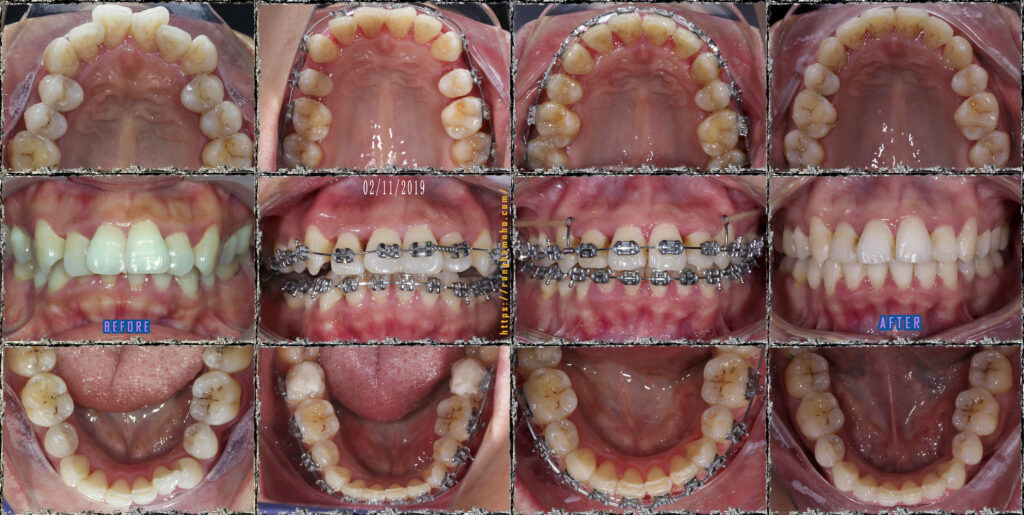

BN sinh năm 1987, đến phòng khám với than phiền hô, nụ cười khấp khểnh, răng chen chúc nhiều. Qua thăm khám đây là một trường hợp hô khá nặng kết hợp cả hô do răng và hô do xương. Nếu mong muốn cải thiện 100% thì BN cần phẫu thuật, cài thiện sau niềng răng đơn thuần chỉ đạt 60-70%.

BN chọn niềng răng đơn thuần với chỉ định nhổ 4 răng số 4, có neo chặn hỗ trợ bằng 2 minivis ở hàm trên.

Sau 2 năm đeo niềng, kết quả trục răng đã thay đổi rất tích cực, tình trạng khớp cắn sâu cũng đã được giải quyết triệt để. Nụ cười cải thiện rõ rệt so với trước niềng.